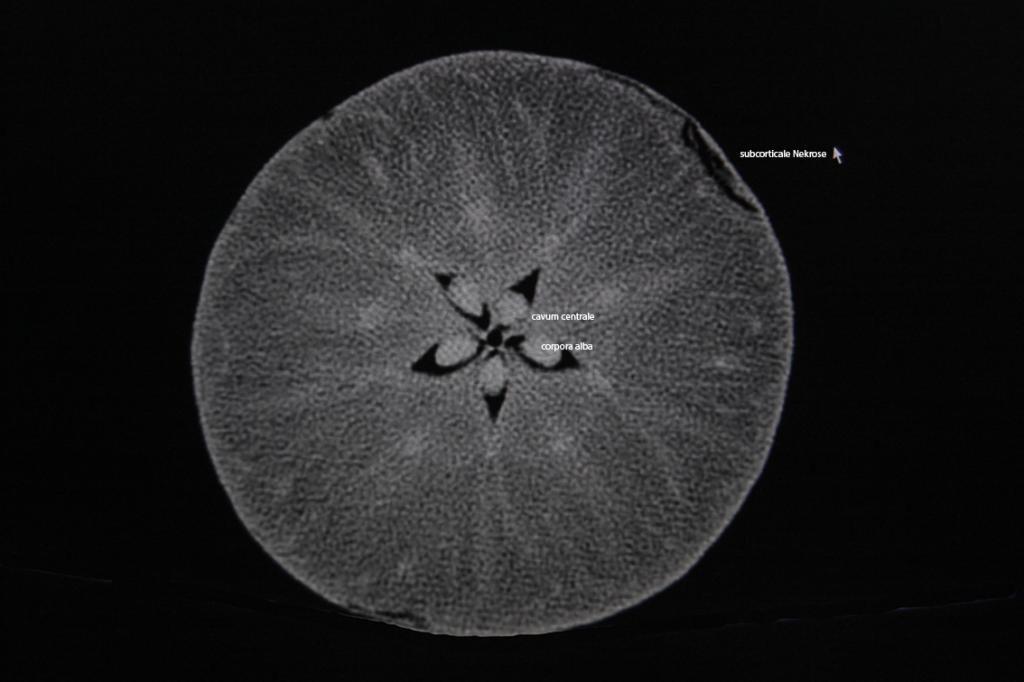

Möglicherweise hat er Interesse an einem Gerät, mit dem man auch Steinobst ( ;D ;D ;D) untersuchen kann: mein Philips "Brilliance Multislice-CT" !